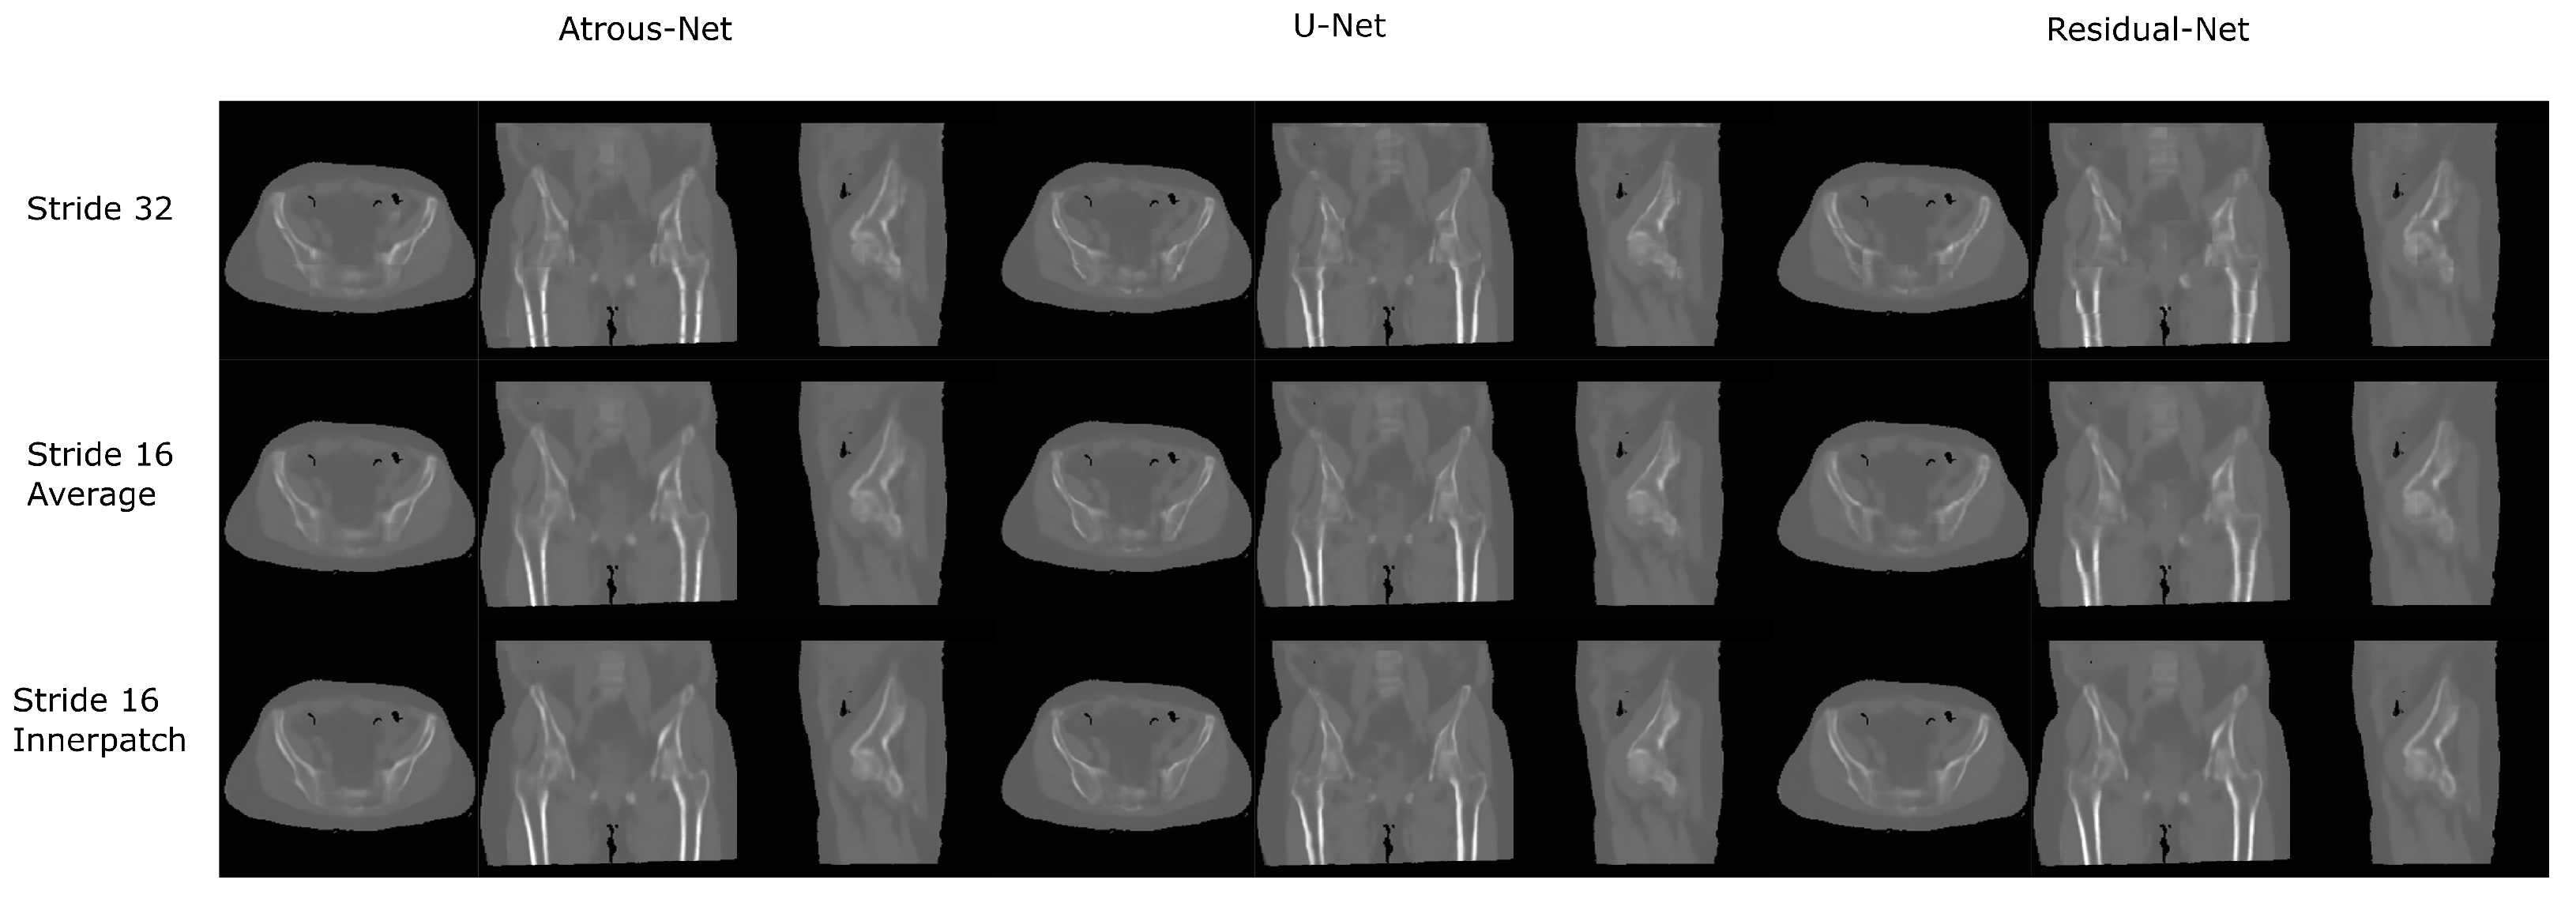

3.2. Pelvis Dataset Results

The results for all tissues using the pelvis dataset are depicted in Table 16, Table 17 and Table 18; the results using only the bone voxels are detailed in Table 19, Table 20 and Table 21; the results using only the fat voxels are detailed in Table 22, Table 23 and Table 24; and the results using only the soft-tissue voxels are detailed in Table 25, Table 26 and Table 27. In the pelvis dataset all networks performed very similar when all tissues were considered. However, 3D networks obtained slightly worse results when assessing bone alone and very similar results for all tissues. The best network in the bone dataset was the 2D Residual network that obtained a MAE of 201.56 HU, a PSNR of 23.20 and a Pearson Coefficient of 0.476 in the bone. Additionally, the error in bone with all networks increased when the 3D scheme was used. The ANOVA test for the 2D results reported a statistically significant effect of the networks in all tissues and bone MAE (all tissues: F 2 , 56 = 6.7 , p < 0.005 ; bone: F 2 , 56 = 8.5 , p < 0.001 ) and PSNR (all tissues: F 2 , 56 = 8.5 , p < 0.001 , bone: F 2 , 56 = 5.3 , p < 0.01 ). According to 3D results, the ANOVA test did not expose statistically significant differences when using different architectures on all tissue MAE (all tissues: F 2 , 56 = 2.3 , p = 0.10 ; bone: F 2 , 56 = 6.2 , p < 0.005 ) and PSNR (all tissues: F 2 , 56 = 1.4 , p = 0.25 ; bone: F 2 , 56 = 4.3 , p < 0.05 ). Post hoc Student’s t-test is depicted in Table 28 and Table 29. It reveals that the Residual-net and Atrous-net did not provide statistically significant differences. Visual result examples of pelvis pseudo-CTs are depicted in Figure 8 and Figure 9. Table 30 shows the time needed to synthesize a whole pelvis volume using the different architectures.

3.4. 3D Reconstruction Results

Figure 10 and Figure 11 show the results of the three merging strategies that have been tested: stride 32, stride 16 with averaging of overlapping voxels and stride 16 considering the inner cube. The average time to synthesize a volume is shown in Table 15 and Table 30. The first method—referred as “stride 32” in Figure 10 and Figure 11—generated artifacts in the boundaries of the cube and misalignment in the bone and air structures. Moreover, this approach showed a greater error than the other two in the quantitative results. Nevertheless, this method was quite fast, generating a volume in 8–19 s. The other two methods provided, in average, a similar quantitative result, being the use of the inner cube slightly better. However, the use of stride 16 increased the time to generate a pseudo-CT volume up to 58–90 s. According to the averaging strategy, some artifacts can be noticed in the boundaries of the cubes after a visual inspection of the results.

Figure 9. Pelvis results using 3D-16 networks.